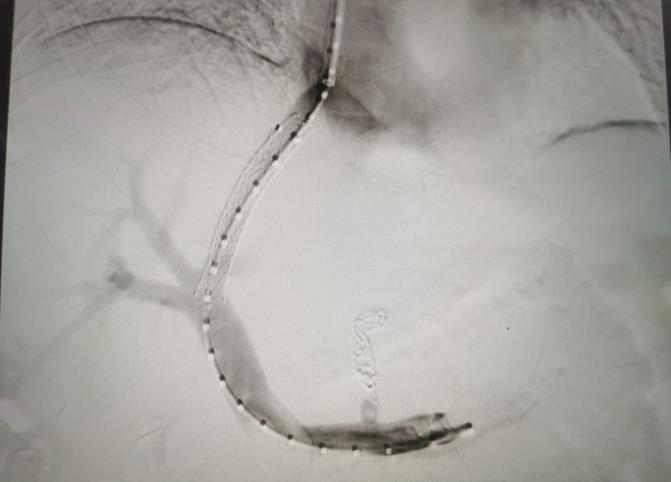

經(jīng)過我院血管介入科醫(yī)療團(tuán)隊(duì)的精心準(zhǔn)備,患者在數(shù)字減影血管造影機(jī)(DSA)導(dǎo)引下,順利經(jīng)頸靜脈入路進(jìn)入下腔靜脈并成功穿刺了門靜脈右支主干,術(shù)中栓塞了曲張的胃冠狀靜脈-食管靜脈叢將支架植入肝實(shí)質(zhì)內(nèi),支架兩端分別置于門靜脈和肝靜脈內(nèi),術(shù)程歷時(shí)2小時(shí),術(shù)中患者時(shí)刻保持清醒,手術(shù)切口僅5毫米,術(shù)后第2天恢復(fù)飲食,腹脹、腹水癥狀明顯好轉(zhuǎn),未出現(xiàn)嘔血、黑便及肝性腦病等并發(fā)癥,術(shù)后第3天康復(fù)出院。